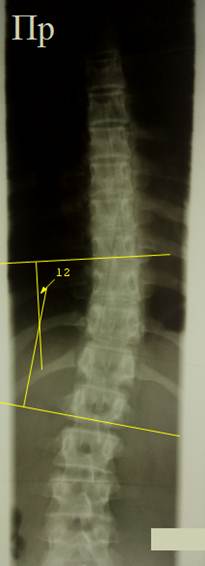

Слева

изображена боковая рентгенограмма

грудного отдела позвоночника ребенка 16 лет с компрессионным переломом 9 и 10

грудных позвонков, уже вами виденная. По методу Кобба выполнено определение

угла клиновидной деформации 10 грудного позвонка (15°), а также угла крудного кифоза (33°). Справа

изображена боковая рентгенограмма грудного отдела позвоночника ребенка 9 лет,

тела грудных позвонков имеют физиологическую клиновидность, что затрудняет

определение угла грудного кифоза по методу Кобба. Выполнено определение угла

грудного кифоза по методу Фергюсона (25°) – просто, изящно,

удобно.